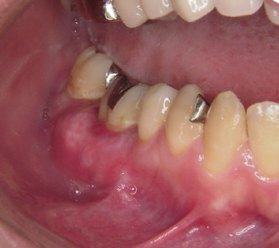

術後1週間です.

歯ぐきが重なっているのが見えます.

この時点で症状はありません.